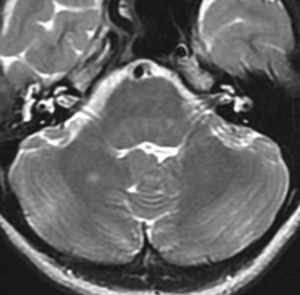

脳幹部のUBOです,大きくなると脳幹部神経膠腫に間違えられることがあります

脳幹部グリオーマと間違えそうなもの

3歳の時に,MRIで脳幹部から小脳のグリオーマを疑われて受診しました。橋が腫れて右小脳にもグリオーマのような白い影があります。でもこれは,NF-1のUBOの大きなものです。びまん性正中グリオーマと誤診されて放射線治療を受けてしまった子供もみたことがあります。治療しなくても縮小していくので,何もしないで経過観察します。右側のMRIは13年後のものです。ほとんど消失しています。